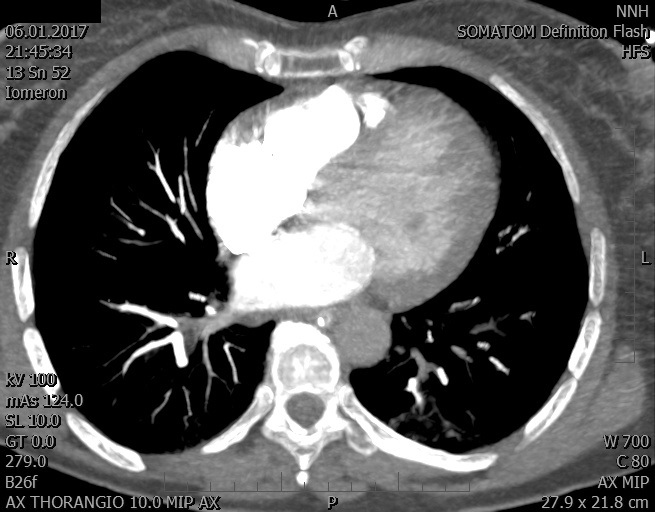

Video 2 - Echokardiograficky byla zjištěna těžká dysfunkce dilatační levé komory s nezvětšenou pravou komorou.Pro nejasnou příčinu zástavy jsme provedli i vyšetření výpočetní tomografií (CT), které vyloučilo plicní embolizaci (série 1 - soubory na konci článku). V den přijetí při přetrvávající oběhové nestabilitě byla nemocná opakovaně defibrilována pro fibrilaci komor se stabilizací rytmu po podání amiodaronu a mesocainu. Dle hemodynamických měření se jednalo o těžký kombinovaný šok. Vstupní laboratorní vyšetření bylo bez větších pozoruhodností. Posléze jsme doplnili anamnézu od příbuzných a zjistili, že pacientka užila do dvou hodin před srdeční zástavou první tabletu amoxicilinu na lehký respirační infekt. Při nevýtěžnosti vstupních vyšetření a nových anamnestických informacích jsme doplnili 14 hodin po kolapsu vyšetření koncentrace tryptázy v séru, která byla extrémně zvýšena (tabulka 2), což nás vedlo k podezření na anafylaxi.